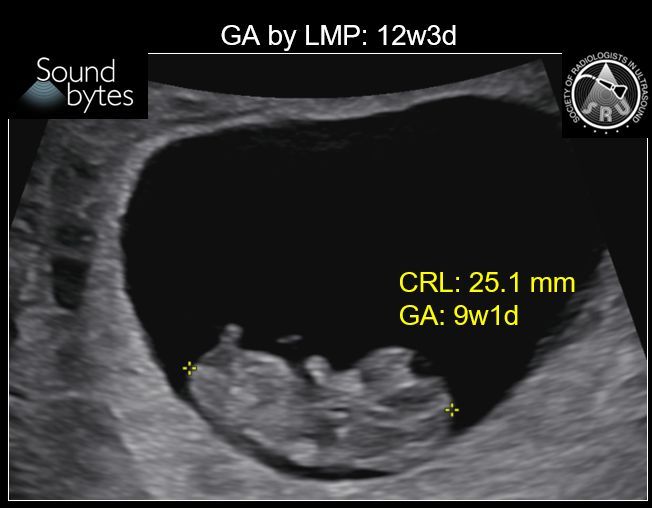

@sruradiology

SRU Radiology

10 days

Answer: Size Date Mismatch Findings: Discrepancy of >7d in GA by LMP vs US late1st T (9 0/7 wk to 13 6/7 wk) suggests size-dates discrepancy, per ACOG guidelines (below). Case courtesy of Dr. April Griffith, U of UT #RadResidents #ultrasound #RadInTraining